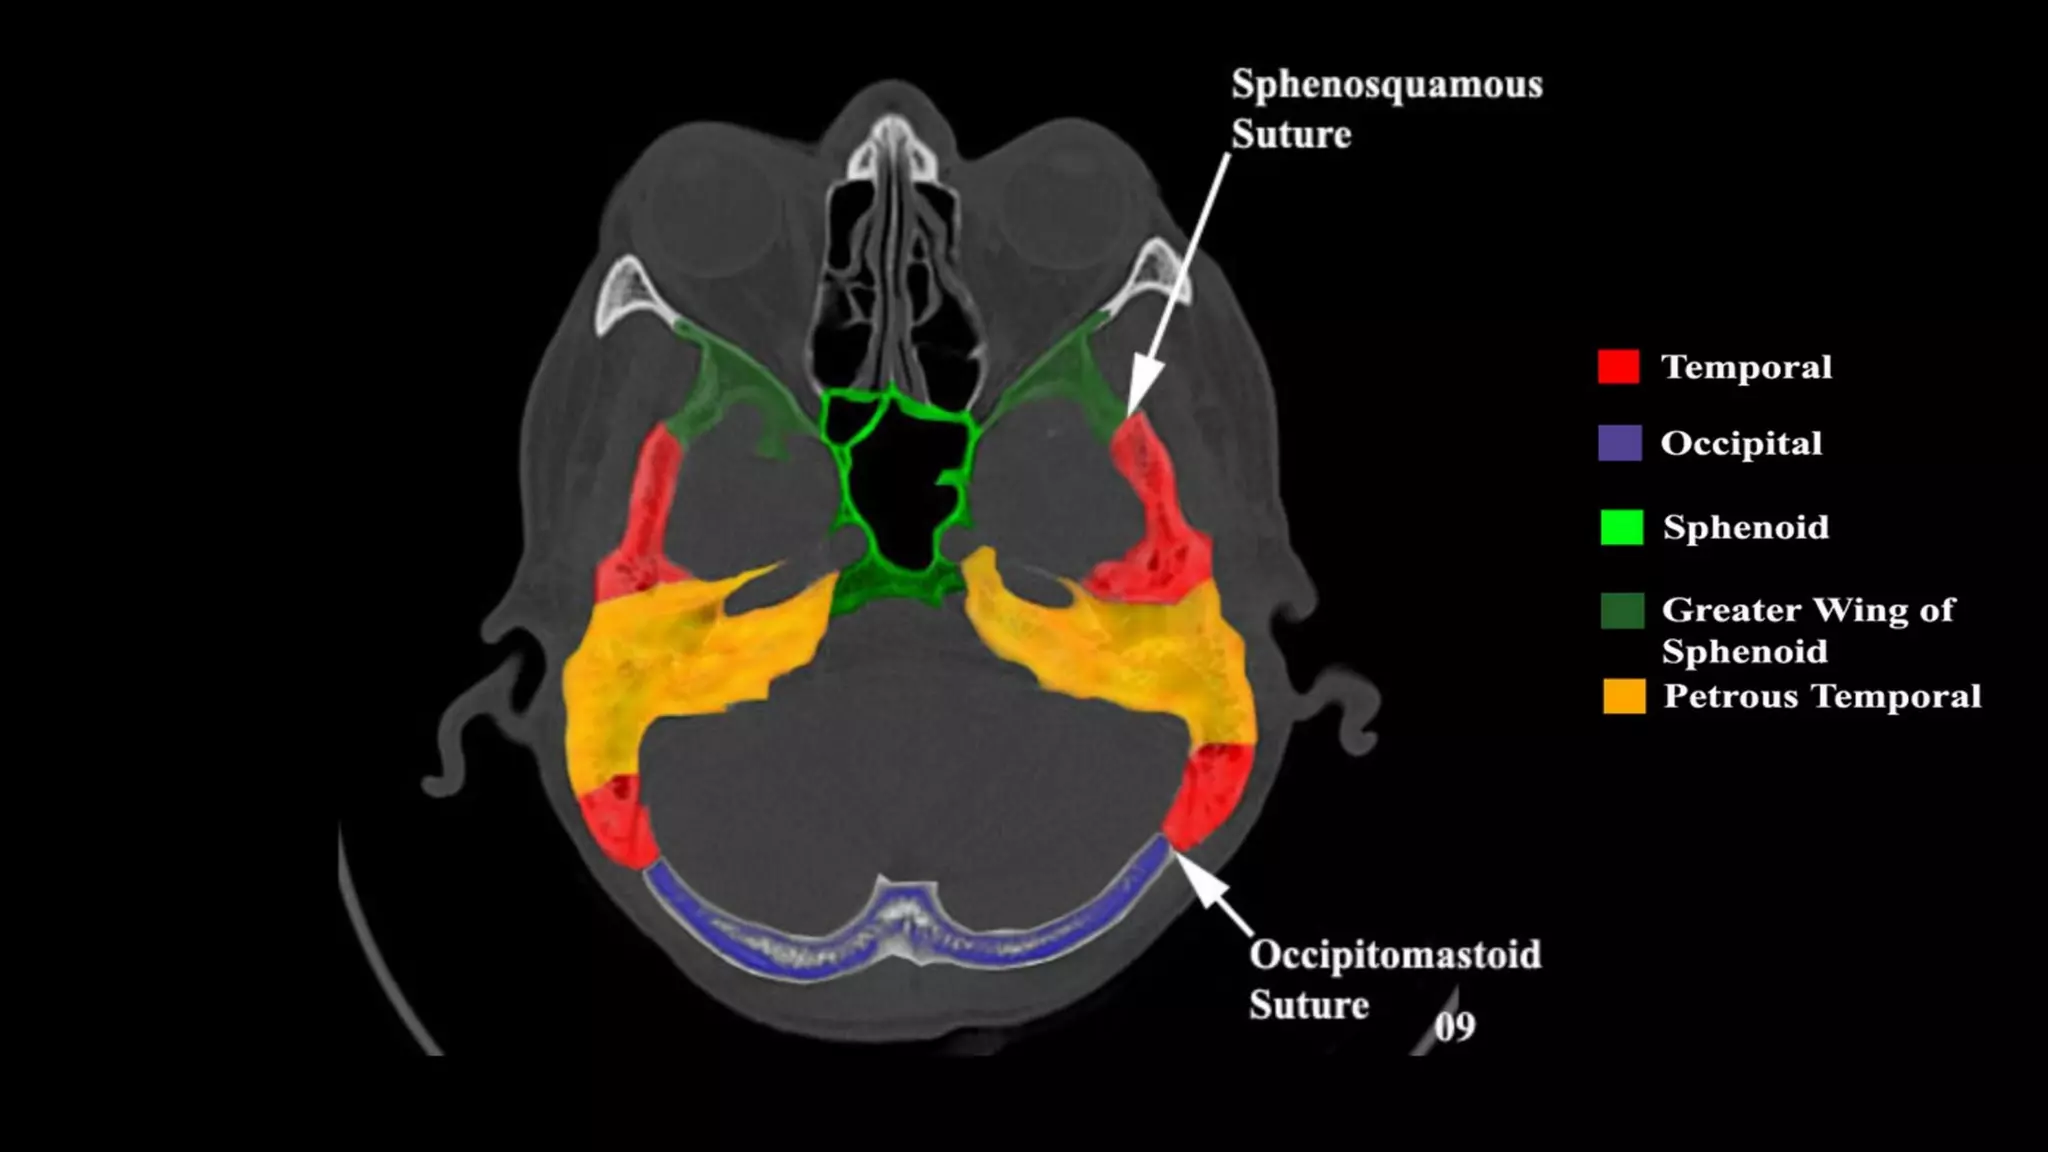

Pseudo-fractures

Extrinsic Fissures &

Sutures